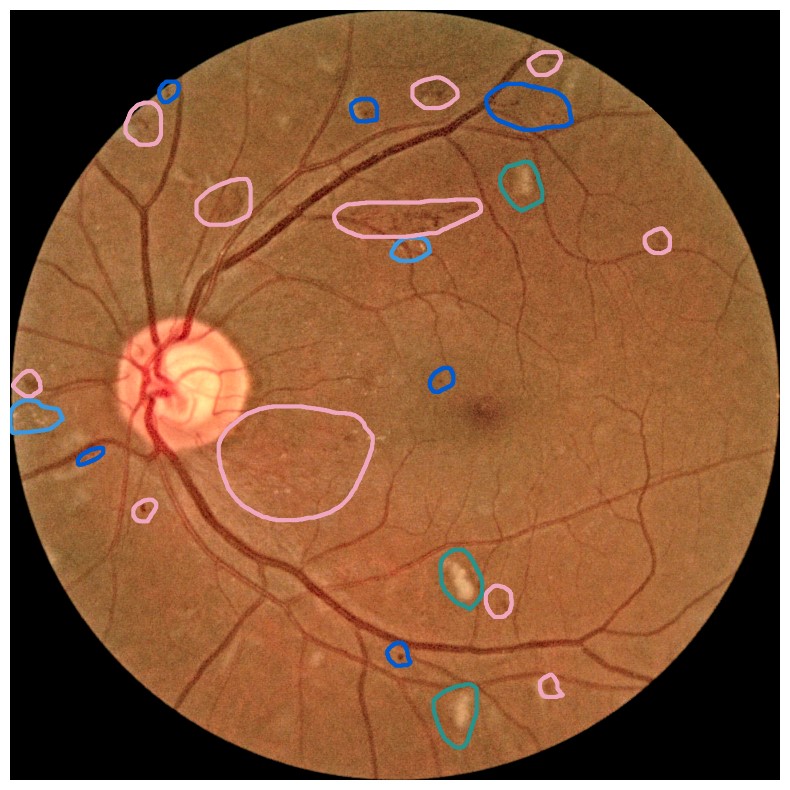

Diabetes is a disease with increasing prevalence, and diabetic retinopathy (DR) is one of the most common complications (World Health Organization, 2022). DR is characterized by retinal abnormalities, which damage the eye and can lead to blindness. Its severity depends on the type and amount of retinal abnormalities: HE, microaneurysms (MA), hard exudates (EX), soft exudates (SE), intraretinal microvascular abnormalities (IRMA), and neovascularization (NV). DR is graded from to (no DR, mild, moderate, and severe nonproliferative DR, and proliferative DR), as described by Wilkinson et al. (2003). DR grading of fundus images is traditionally a manual process requiring medical expertise. Figure 1 provides examples of fundus images of eyes with increasing severity of DR including the ground truth segmentations of the six retinal abnormalities. These images underline the challenge of identifying relevant medical abnormalities without specialist training.

Concept explanation methods are attractive for medical applications because they measure how much the deep neural networks are influenced by high-level concepts representing clinical findings (Salahuddin et al., 2022). A concept can be described as a theme or topic, e.g., ’stripes’ and ’dots’ for natural images, or diagnostic findings such as ’hemorrhages’ and ’microaneurysms’ for fundus images. The six different diagnostic concepts used for this work is shown with the ground truth segmentation masks in Figure 1. TCAV (Kim et al., 2018) and Concept Bottleneck Models (Koh et al., 2020) are two concept-based methods that have several advantages above heatmap methods. Both allow the user to define the concepts, which ensures relevant and meaningful concepts that are interpretable for the end-users. How the concepts are used varies between the two explanation methods and is outlined in Sections 2.1 and 2.2. Moreover, the relative importance of the concepts can be quantitatively measured. For Testing with Concept Activation Vectors (TCAV), concept scores can be generated for a group of images, e.g. images belonging to the same class, allowing the user to investigate whether the model has learnt aspects coherent to domain knowledge and diagnostic guidelines. CBMs, on the other hand, allow the user to directly modify the model’s intermediate concept predictions at test time and observe how this affects the final model prediction. This way of manipulating the model after training is attractive in the medical field, e.g. if the clinician wants to increase the emphasis of a concept in the image that the model missed. While TCAV explains models post-hoc, i.e., predicting the concepts after the classification model has been trained, CBMs provide ad-hoc explanations, where the prediction of the concepts are trained together with the classification model. Even though concept explanations can be more intuitive than heatmaps for medical doctors, neither TCAV or CBMs have been extensively studied in the field of DR grading. In this work, we thus investigate and compare TCAV and CBMs for explaining deep neural networks trained to grade DR in fundus images.